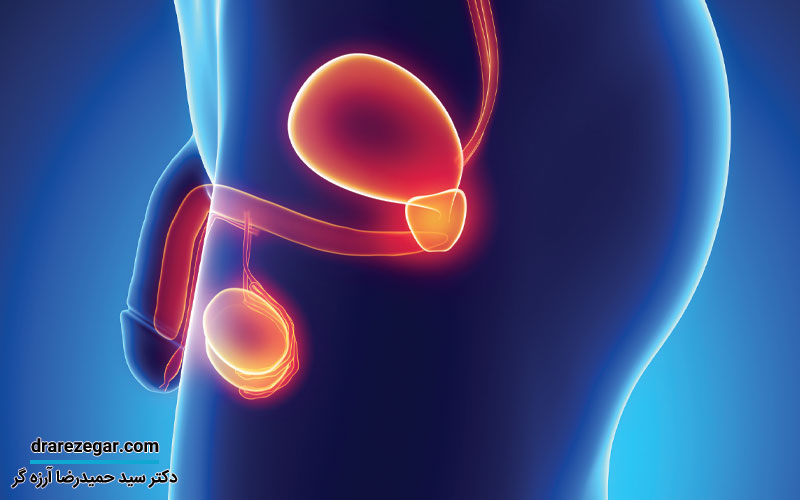

بزرگی بدخیمی پروستات

بزرگی پروستات یکی از مشکلات شایع در میان مردان، به ویژه در سنین بالاتر، است. بدخیمی پروستات ممکن است کاملا بی علامت باشد و در آزمایش و معاینه مشخص شود. این عارضه می تواند به دو دسته خوش خیم و بدخیم تقسیم شود. نوع خوش خیم آن که بیشتر به عنوان هیپرپلازی خوش خیم پروستات (BPH) شناخته می شود، معمولاً با علائمی مانند مشکلات ادراری و نیاز مکرر به تخلیه مثانه همراه است. در مقابل، نوع بدخیم آن که به سرطان پروستات معروف است، می تواند علائم شدیدتر و پیچیده تری داشته باشد و نیاز به روش های درمانی مختلفی داشته باشد که بر اساس میزان پیشرفت و شدت بیماری تعیین می شوند. در این مقاله به بررسی بزرگی بدخیمی پروستات، علل ابتلا به آن، روش های درمان و معرفی بهترین پزشک برای تشخیص و درمان آن می پردازیم.

بزرگی بدخیمی پروستات چیست؟

بزرگی بدخیم یا سرطان پروستات یکی از بیماری های جدی و نگران کننده در مردان است که به ویژه در افراد سالمند یا بالای 65 سال شایع تر است. هر ساله، هزاران نفر در این گروه سنی به این بیماری مبتلا می شوند. سرطان پروستات به رشد توده یا غده سرطانی در پروستات اشاره دارد که می تواند با سرعت های مختلف رشد کند. این بیماری به دو نوع تهاجمی و غیر تهاجمی تقسیم می شود. نوع تهاجمی آن می تواند به سرعت به بافت های مجاور مانند لگن و روده سرایت کرده و آن ها را درگیر کند. سرطان پروستات اغلب در مراحل اولیه بدون علامت است و بسیاری از افراد ممکن است تا زمان پیشرفت بیماری از وجود آن آگاه نباشند. با این حال، با گذشت زمان، مشکلات ادراری مانند تکرر ادرار، سختی در تخلیه مثانه و درد می تواند به نشانه های اولیه بیماری تبدیل شود. تشخیص زودهنگام و درمان مناسب می تواند تفاوت بزرگی در مدیریت و کنترل این بیماری ایجاد کند.